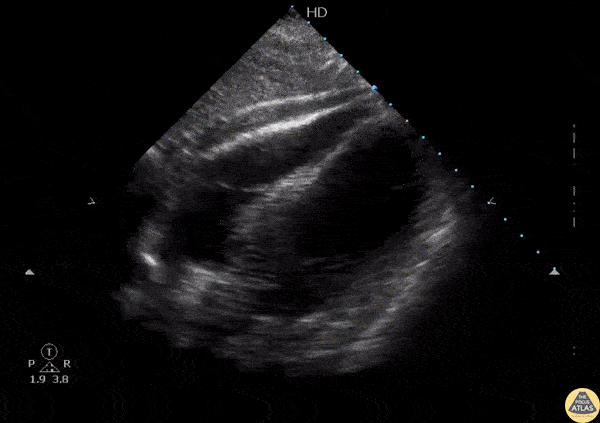

POCUS revealed isoechoic fluid within the pericardium indicative of a hemopericardium in a patient suffering from a gunshot wound. Image courtesy of Robert Jones DO, FACEP @RJonesSonoEM Director, Emergency Ultrasound; MetroHealth Medical Center; Professor, Case Western Reserve Medical School, Cleveland, OH View his original post here